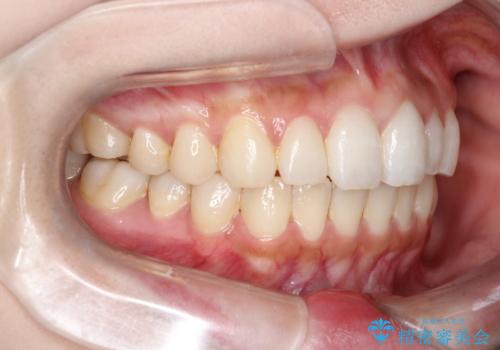

【インビザライン】矮小歯を有する方の治療②

- 前歯の凸凹を主訴に来院されました。

左上の前歯が元々小さいため、前歯の真ん中が揃わないことを伝えた上で矯正治療を開始しています。

スペースを作るために遠心移動ろIPRをおこなて治療を行いました。